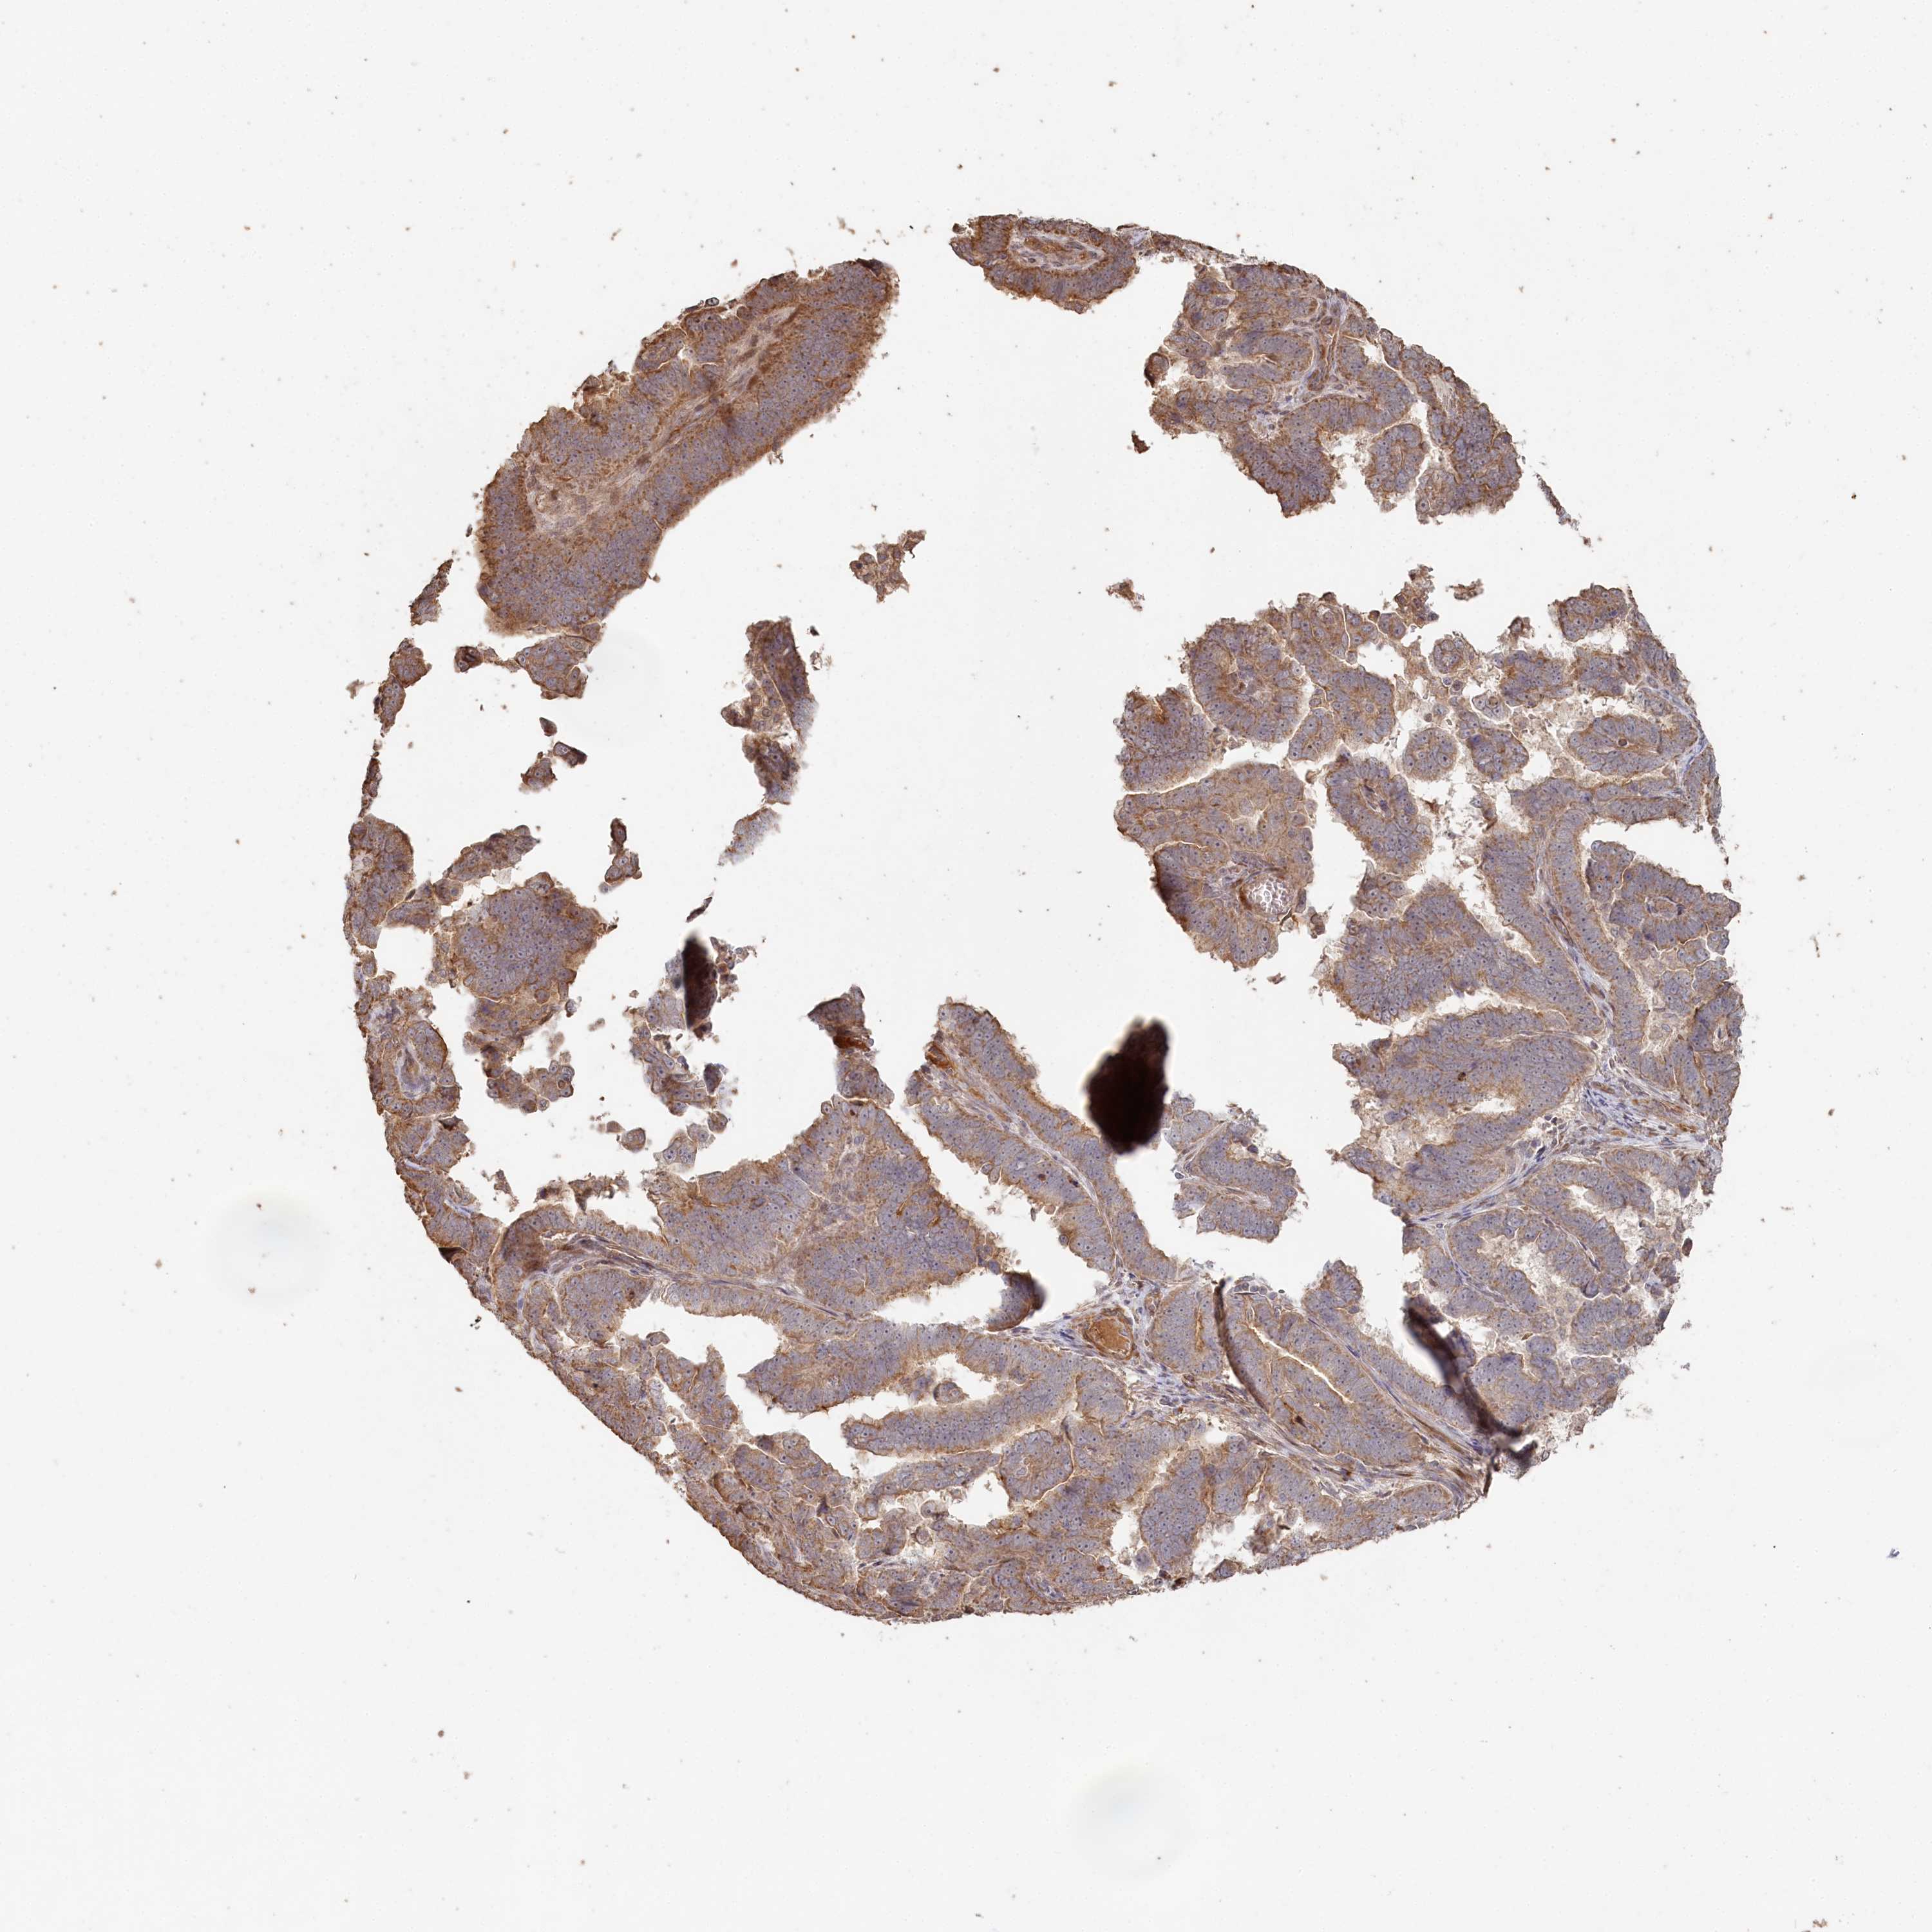

ENDOMETRIAL CANCER - Protein expressioni

A mouse-over function shows sample information and annotation data. Click on an image to view it in a full screen mode. Samples can be filtered based on level of antibody staining by selecting one or several of the following categories: high, medium, low and not detected. The assay and annotation is described here.

Note that samples used for immunohistochemistry by the Human Protein Atlas do not correspond to samples in the TCGA dataset.

Antibody stainingi

Antibody staining in the annotated cell types in the current human tissue is reported as not detected, low, medium, or high, based on conventional immunohistochemistry profiling in selected tissues. This score is based on the combination of the staining intensity and fraction of stained cells.

Each image is clickable and will lead to virtual microscopy that enables deeper exploration of all samples and also displays staining intensity scores, fraction scores and subcellular localization as well as patient and tissue information for each sample.

Antibody HPA038547

Antibody HPA038548

Staining

High

Medium

Low

Not detected

Intensity

Strong

Moderate

Weak

Negative

Quantity

>75%

75%-25%

<25%

None

Location

Nuclear

Cytoplasmic/membranous

Cytoplasmic/membranous,nuclear

Adenocarcinoma, NOS